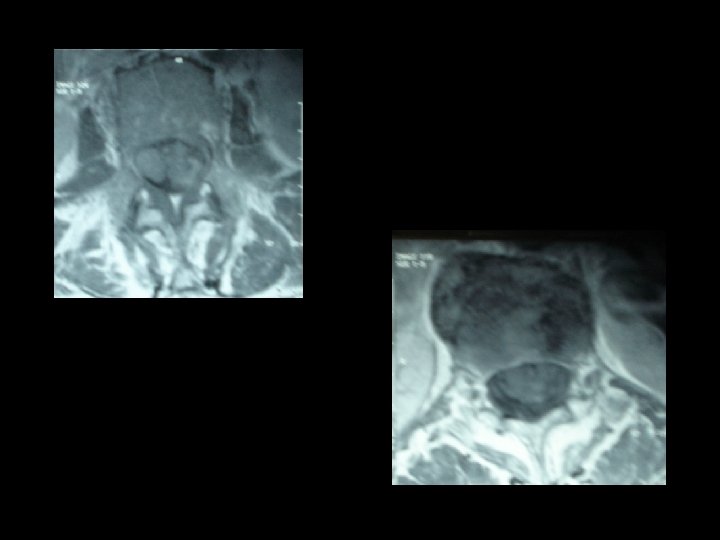

* Les examens biologiques misent en évidence une thrombopénie , une hypo albuminémie et une hypergammaglobulinémie modérée. Sérologie VIH était négative. * L’IRM lombaire pratiquée en séquence T 1, T 2 et avec injection du gadolinium montre un important épaississement des racines de la queue de cheval visible sur les coupes en séquence. T 2 qui se rehaussent intensément après injection du gadolinium.

* La présentation clinique n’est pas spécifique. * IRM médullaire : processus expansif étagé comprimant la moelle par endroit. * les lésions sont e hypo signal T 1, hyper signal T 2 et se rehaussant après injection du gadolinium. * l’IRM joue un rôle primordial dans le diagnostic des lymphomes à localisation médullaire.